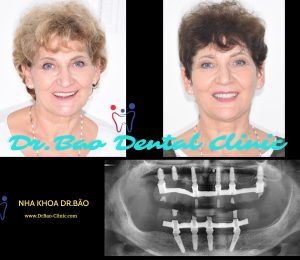

FULL MOUTH REHALIBITATION – RESTORE FUNCTION AND COSMETIC

A male customer (40 years old), visited Dr.Bao Dental Clinic to check and he want to make his teeth healthier and stronger.

A male customer (40 years old), visited Dr.Bao Dental Clinic to check and he want to make his teeth healthier and stronger.

After check up clinician and X-ray:

After check up clinician and X-ray:

– All his teeth were prepared for crowns.

– Gum got inflamation and bleeding a lot whenever he brushed his teeth.

– Teeth were sensitive with water, even normal water.

THE TREATMENT PLAN INCLUDING MANY STEPS:

THE TREATMENT PLAN INCLUDING MANY STEPS:

– Periodontal disease treatmetn.

– Remove all his old crowns.

– Remove the hopeless teeth.

– Design full mouth rehalibitation and restore by implants and zirconia crowns.